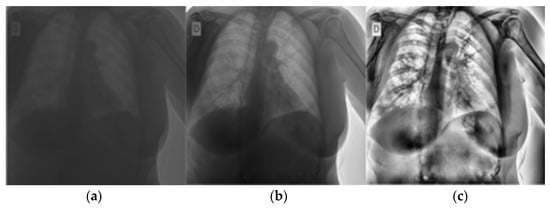

A total of 3330 CXRs were used to train and test the CNN models. Each CXR corresponded to a unique patient. The training and testing dataset contains 632 images of COVID-19+ patients, 1592 images of healthy patients, and 1106 images of patients with non-COVID-19 pneumonia. Considering that normal images significantly outnumbered both pneumonia and COVID-19 images, the 1592 normal images were chosen at random from all images that could have been included. An additional 836 images were kept for validating the ensemble model, of which 160 were COVID-19 images, 406 were of healthy patients and 269 belonged to patients with pneumonia. The count of CXRs is shown in Table 1. The three classes of images will be referred to as COVID-19, normal, and pneumonia, respectively for the rest of the paper. Example CXRs are shown in Figure 2.

Figure 2.

Sample of COVID-19, pneumonia and normal CXRs used in training and testing the model.